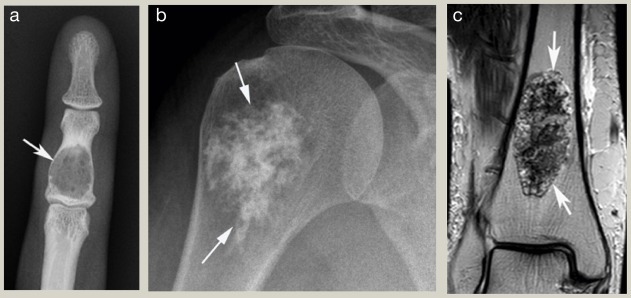

روش های تشخیص تومور های استخوانی

تشخیص دقیق تومور های استخوانی نیازمند بررسی کامل توسط متخصص ارتوپدی و انکولوژی است. پزشک معمولا پس از گرفتن شرح حال بیمار و معاینه فیزیکی از روش های تصویربرداری و آزمایشگاهی استفاده می کند. مهم ترین روش های تشخیصی عبارتند از:

- عکس رادیولوژی یا اشعه ایکس

اولین روش برای بررسی استخوان و مشاهده تغییرات ناشی از تومور است. این تصاویر می توانند نشان دهند که آیا استخوان ضعیف یا تخریب شده است یا خیر. - سی تی اسکن (CT scan)

این روش جزئیات بیشتری از ساختار استخوان نشان می دهد و به پزشک کمک می کند اندازه و محل دقیق تومور را بررسی کند. - ام آر آی (MRI)

ام آر آی یکی از بهترین روش ها برای بررسی بافت های نرم اطراف استخوان و میزان گسترش تومور است. - اسکن استخوانی (Bone Scan)

تومور های استخوانی مجموعه ای متنوع از بیماری ها هستند که از رشد های خوش خیم و بی خطر تا سرطان های خطرناک را شامل می شوند. شناخت علائم اولیه، آگاهی از انواع تومور استخوانی و توجه به روش های تشخیص علمی از جمله رادیولوژی، سی تی اسکن، ام آر آی و بیوپسی می تواند به بیماران کمک کند در مراحل ابتدایی به پزشک مراجعه کنند.

تشخیص دقیق تومور با استفاده از روش های پیشرفته تصویربرداری مانند رادیولوژی، سی تی اسکن و ام آر آی انجام می شود. نمونه برداری و بررسی بافت از اهمیت بالایی برای تعیین خوش خیم یا بدخیم بودن تومور برخوردار است.